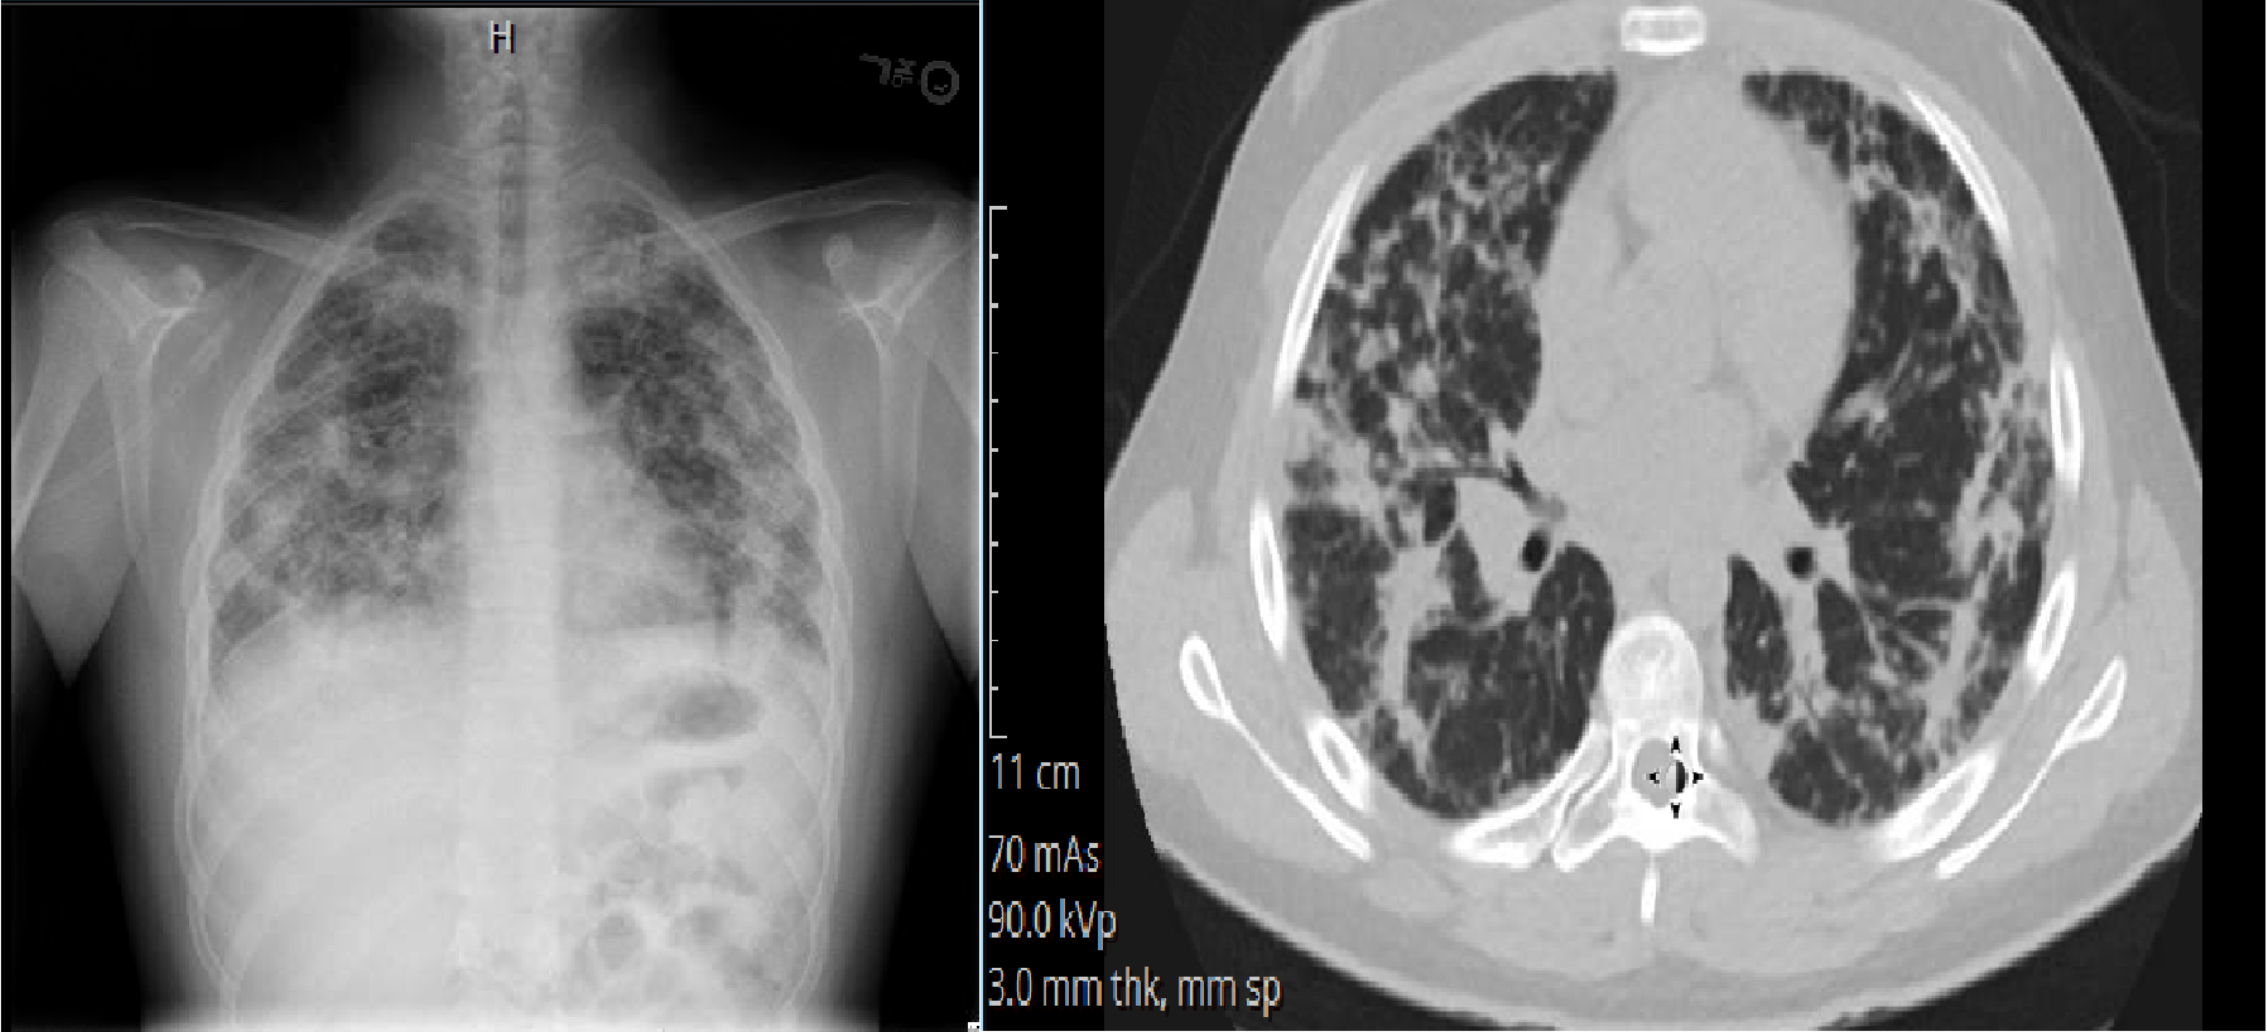

In the emergency room, he was febrile to 38.3 C, tachycardic and tachypneic. He had hypoxia that improved with supplemental oxygen. On exam, he appeared ill with increased work of breathing and had crackles bilaterally. Labs showed WBC 20.8 (absolute eosinophil count 1430), ESR 85, CRP 22.2 and IgE 151. Chest x-ray showed bilateral pulmonary infiltrates most prominent in the peripheral fields. High resolution chest CT showed predominantly peripheral opacification, nodules and reticulations in the lungs. Bronchoscopy with lavage showed 7 WBC and 0% eosinophils; PCRs for bacteria and viruses were negative. Culture grew rare oral flora. Sulfasalazine was discontinued shortly after admission. Pathology from open lung biopsy showed acute/subacute eosinophilic pneumonia without infection or vasculitis. Work-up was negative for various causes of pulmonary eosinophilia including vasculitis, fungi and helminths. He was diagnosed with sulfasalazine-induced acute eosinophilic pneumonia and was treated with three days of IV methylprednisolone prior to discharge, followed by a three month taper of prednisone with resolution of the disease. He has not relapsed off prednisone.

IMAGE 1: Lung Imaging